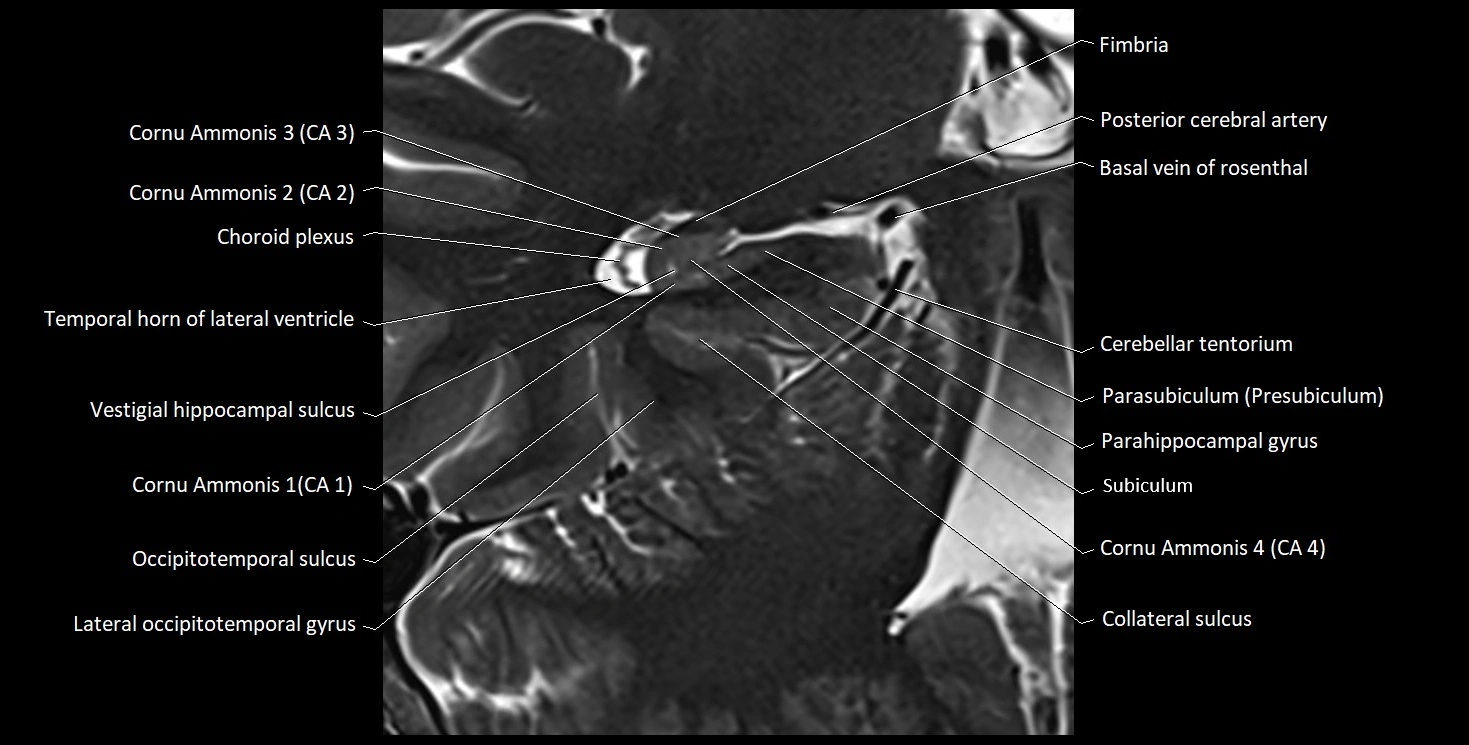

MRI Appearance

T1-weighted images:

• Alveus: Thin linear high signal band (due to myelinated fibers) overlying the hippocampal gray matter.

• Hippocampal gray matter: Intermediate signal intensity.

• CSF of lateral ventricle: Dark (low signal).

T2-weighted images:

• Alveus: Low signal line overlying brighter hippocampal gray matter.

• CSF: Bright hyperintense.